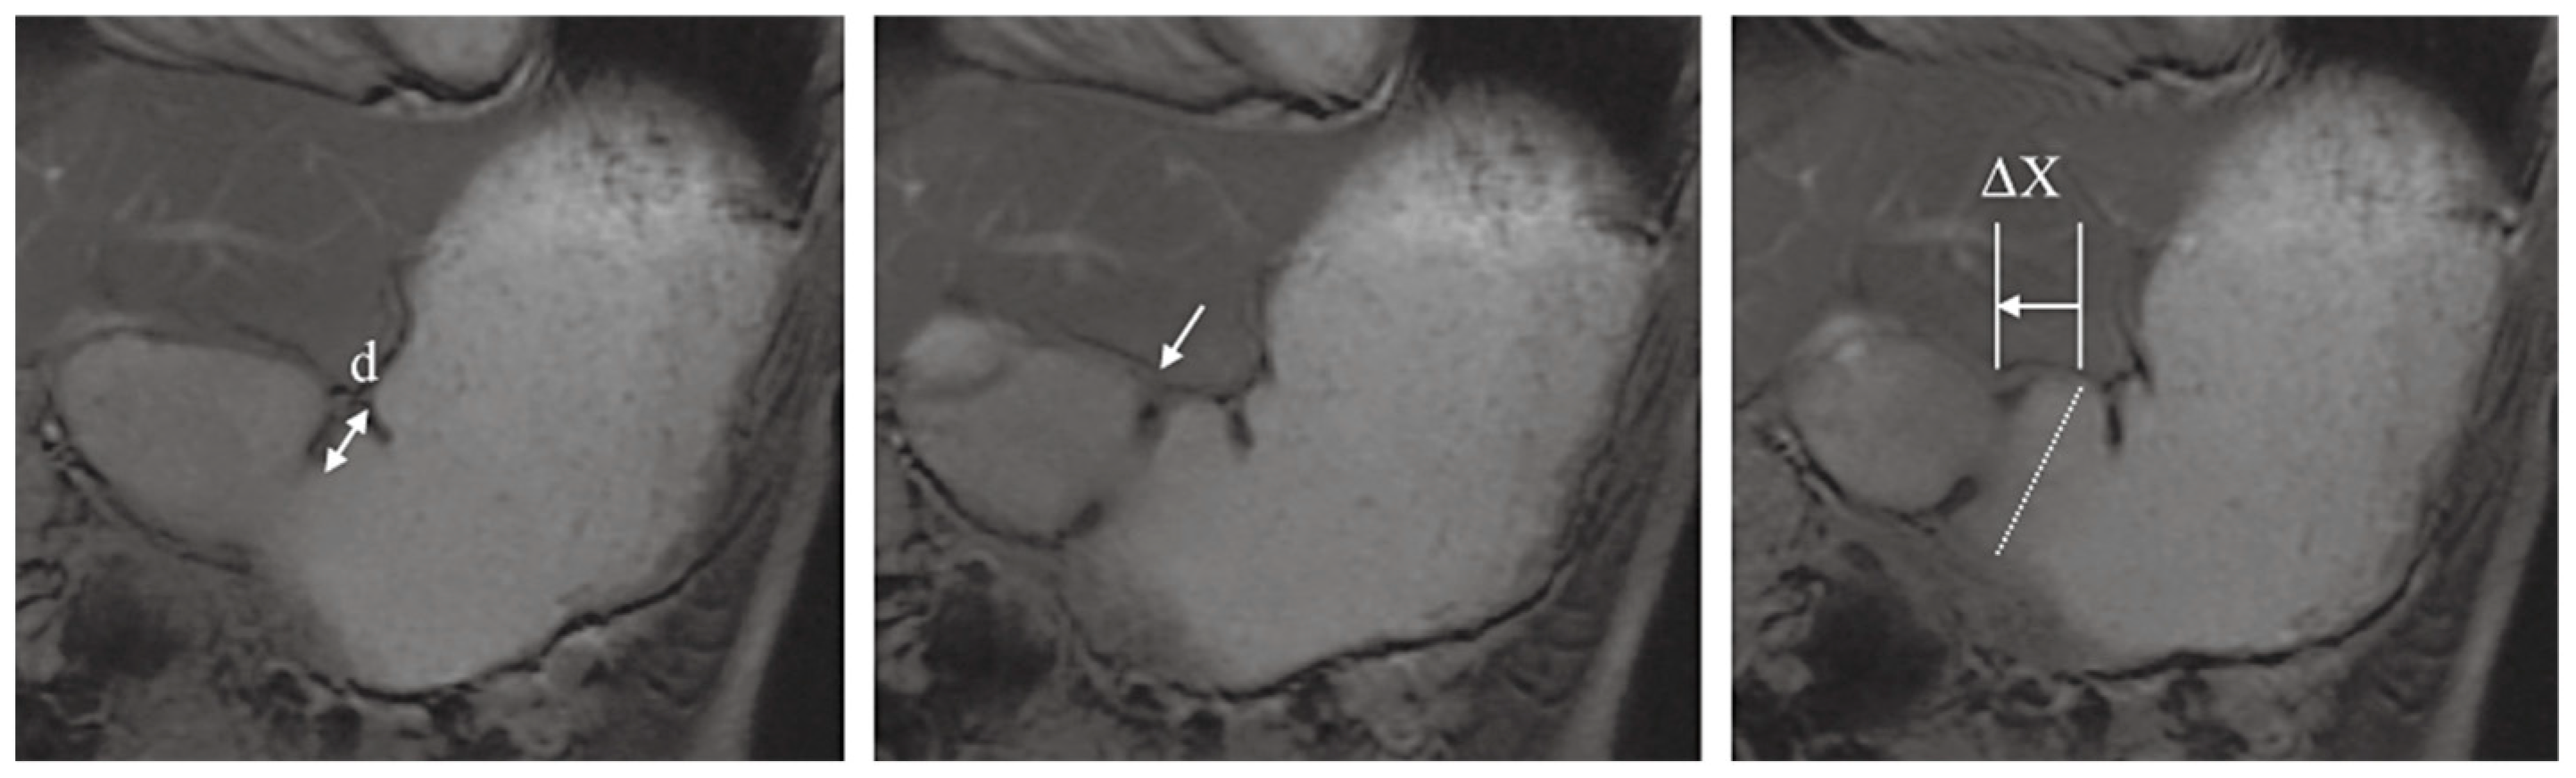

- Kwiatek, M.A.; Steingoetter, A.; Pal, A.; Menne, D.; Brasseur, J.G.; Hebbard, G.S.; Boesiger, P.; Thumshirn, M.; Fried, M.; Schwizer, W. Quantification of Distal Antral Contractile Motility in Healthy Human Stomach with Magnetic Resonance Imaging. J. Magn. Reson. Imaging 2006, 24, 1101–1109. [Google Scholar] [CrossRef]

- Marciani, L.; Gowland, P.A.; Fillery-Travis, A.; Manoj, P.; Wright, J.; Smith, A.; Young, P.; Moore, R.; Spiller, R.C. Assessment of Antral Grinding of a Model Solid Meal with Echo-Planar Imaging. Am. J. Physiol. Gastrointest. Liver Physiol. 2001, 280, G844–G849. [Google Scholar] [CrossRef] [PubMed]